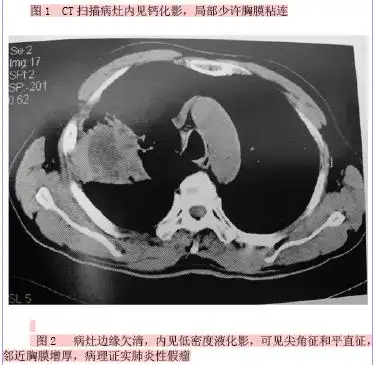

【病例】肺炎性假瘤1例ct影像讨论

左肺炎性假瘤

肺炎性假瘤x线ct表现